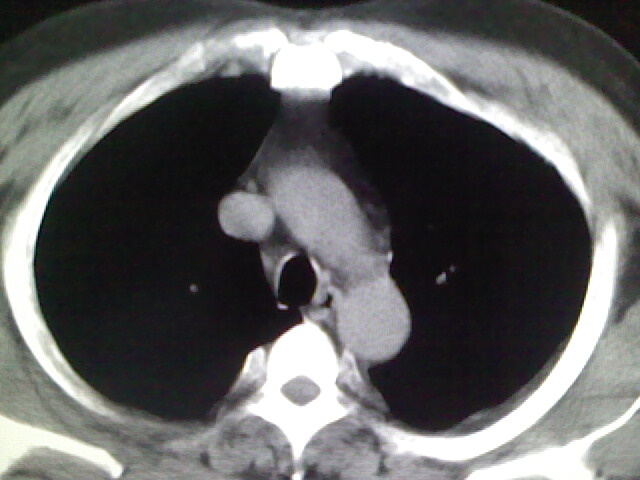

标题: CT17932:临床怀疑肺栓塞

男,34岁,自觉右侧胸痹,胸闷3天余

左上肺局限片状透光度增强区,肺纹理稀少,可考虑局限性肺气肿。

左上肺局限性肺透光度减低,肺纹理稀少;这虽然符合早期肺栓塞的改变,但与局限性肺气肿难以鉴别。

书上讲早期肺栓塞就是表现肺透光度减低,肺纹稀少。